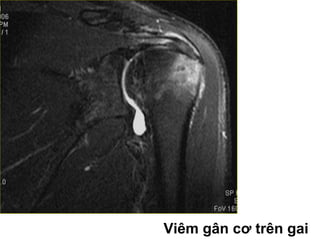

Vieâm gaân

• Gaân khoâng giaûm beà daøy, taêng tín hieäu

treân T2W beân trong gaân, möùc ñoä tín hieäu

taêng ít hôn tín hieäu dòch khôùp.

Viêm gân cơ trên gai

Vieâm gaân • Gaânkhoâng giaûm beà daøy, taêng tín hieäu treân T2W beân trong gaân, möùc ñoä tín hieäu taêng ít hôn tín hieäu dòch khôùp.

Viêm gân cơtrên gai